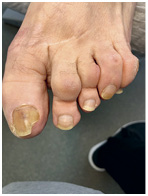

Иллюстрация к книге — Подология понятно. Важен каждый шаг. Справочник по проблемам подологии для клиентов и мастеров эстетики [i_269.jpg]

Иллюстрация к книге — Подология понятно. Важен каждый шаг. Справочник по проблемам подологии для клиентов и мастеров эстетики [i_270.jpg]

Иллюстрация к книге — Подология понятно. Важен каждый шаг. Справочник по проблемам подологии для клиентов и мастеров эстетики [i_271.jpg]

Иллюстрация к книге — Подология понятно. Важен каждый шаг. Справочник по проблемам подологии для клиентов и мастеров эстетики [i_272.jpg]

Результат работы за 5 месяцев: подолог использовал крючковые коррекционные системы, а хирург сделал пластику внутреннего бокового валика (из-за хронических воспалений боковой валик стал гипертрофированным и давил на ноготь, от чего клиент испытывал постоянный дискомфорт)